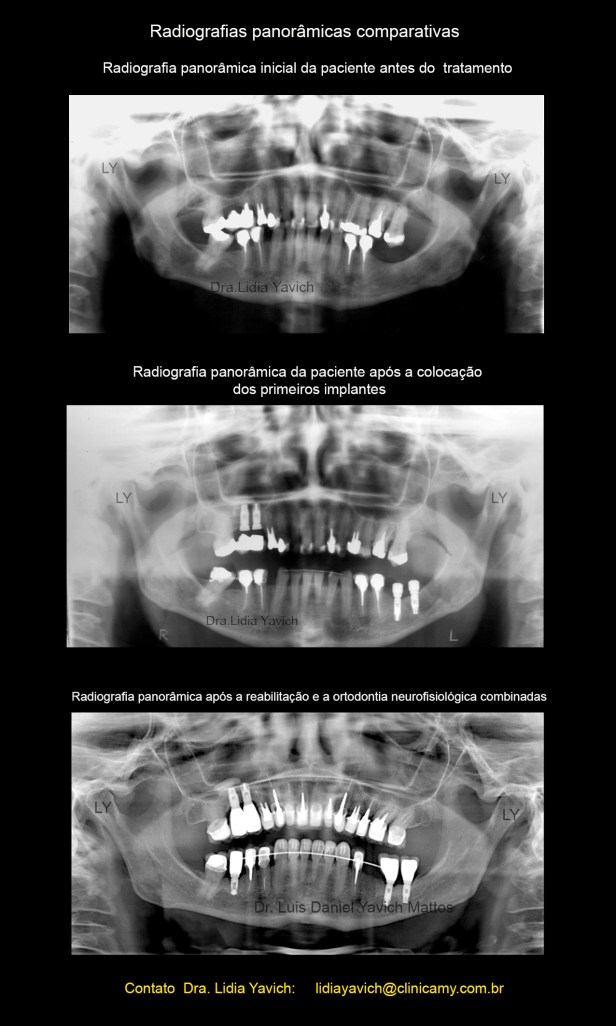

Ao exame radiográfico obseva-se ausência dos elementos dentais 18,16,28,28,36, 46 4 48.

Os elementos 15, 14, 22, 24, 26, 35,44 e 45 se encontram endodonticamente tratados.

Presença de prótese fixa com apoio nos elementos 16/15. Presença de prótese fixa unitária com pino metálico intracanal nos elementos 14, 22, 26, 35,34 e 45.

Extensa restauração coronária nos elementos 13,24 e 44.

Presença de material restaurador nos elementos 11, 21, 23, 27,32 e 47.

Perda óssea alveolar na maxila e na mandíbula mais acentuada nas áreas edêntulas.

Alongamento do processo estiloide esquerdo.

Foi planejada a instalação de dois implantes no lado esquerdo inferior e dois implantes no lado direito superior onde a paciente tinha uma prótese velha.

Radiografias panorâmicas comparativas: inicial antes do tratamento em oclusão habitual e a panorâmica com os implantes colocados, com o DIO, dispositivo intraoral em posição neuromuscular fisiológica instalado em boca.

Implante no lugar do 46, após a recuperação do espaço.

Implante no lugar do 46, após a recuperação do espaço.

Radiografia panorâmica com a finalização da reabilitação e o espaço do dente 35 preservado para futuro implante.

Comparação das radiografias panorâmicas pré, durante e após a reabilitação neuromuscular fisiológica combinada com a ortodontia tridimensional.